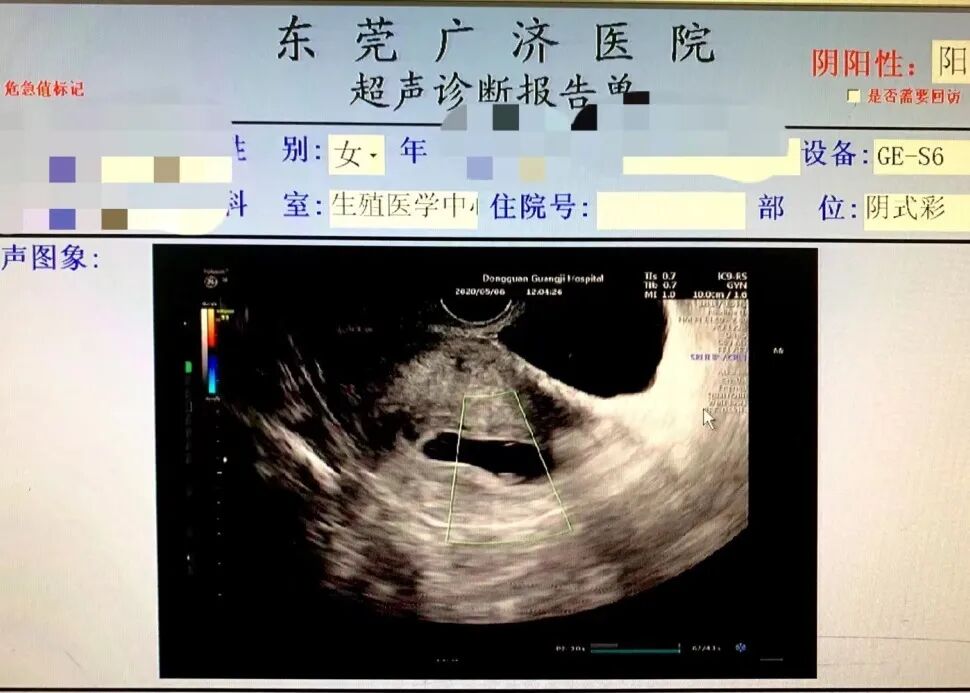

6周B超结果

2022年1月26日:B超提示宫内单胎妊娠